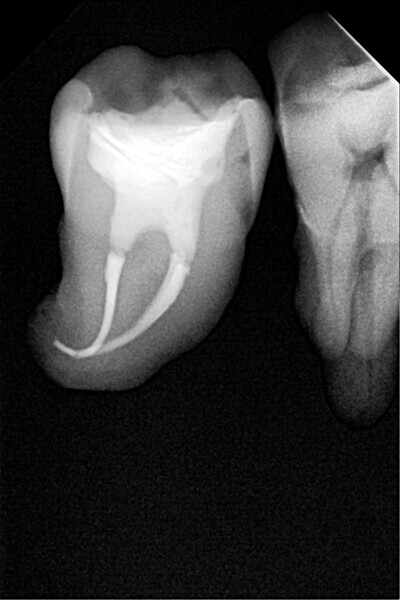

1. functional and aesthetic reconstruction of a maxillary anterior tooth using fibre-reinforced flexible micro-posts after endodontic treatment (Figs. 3–20);

Example 1—showing functional and aesthetic reconstruction of a maxillary anterior tooth using fibre-reinforced flexible micro-posts after endodontic treatment.

1. direct restoration using a fibre-reinforced flowable composite and membrane cube after endodontic treatment (Figs. 21–35); and